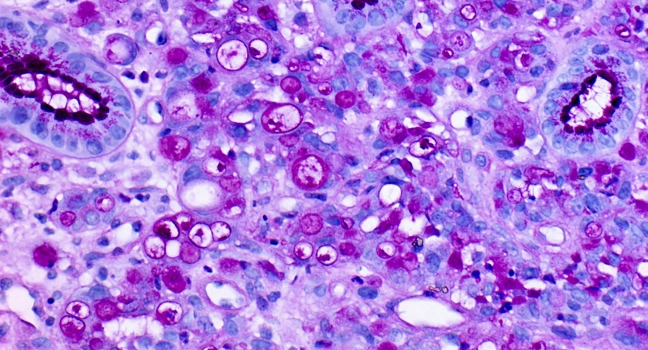

Iedere patiënt verdient de beste behandeling en die begint bij de juiste diagnose. Voor het stellen van de juiste diagnose is inzicht in de voorgeschiedenis van de patient van eerder cel- en weefselonderzoek een grote toegevoegde waarde. De data hiervan moeten veilig en gestructureerd worden opgeslagen en beschikbaar zijn voor de behandelende patholoog. Op deze manier kan de patholoog met volledige inzicht vanuit de pathologie, informatie bijdragen aan het behandelteam.